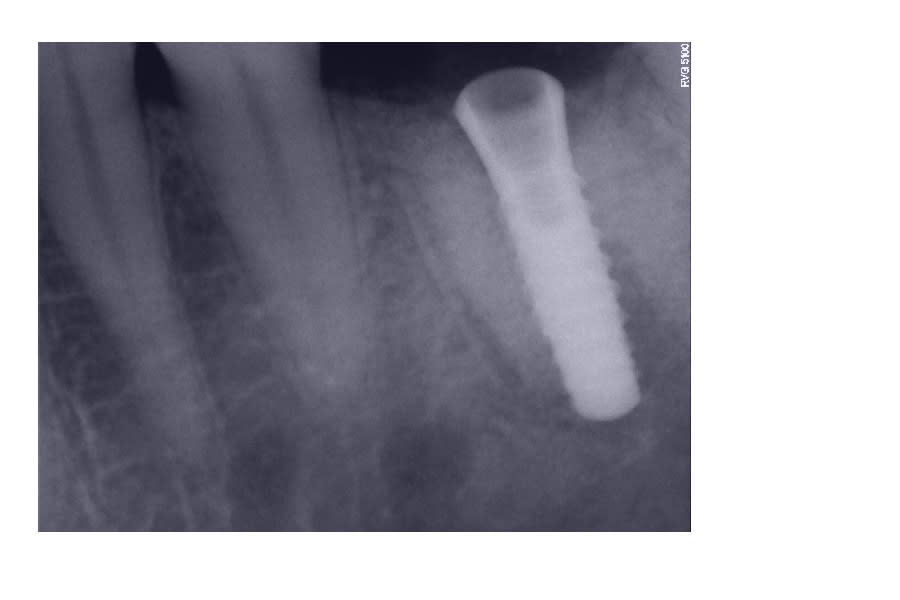

vu ce matin ce patient avec cet implant posé il y a 18 mois

par un confére,j'ai cru que c'étaient les racines que l'on voyait,mais je pense plutôt pour un comblement qui n'est pas trés réussi,quelle est la marque de l'implant et pensez vous qu'il est viable

oui c'est bien un straumann...certainement en 4.1mm

les radios sont pas très très bonnes...çà peut aussi être un Zimmer swissplus...

c'est de toutes façons le même type de connexion octogonale...

Sur les Straumann, l'apex est plus arrondi, les spires plus espacées...

C'est pas un Straumann.

Le tissue Level a effectivement des spires plus espacées et l'apex est rond.

De plus,le col est plus en pavillon de trompette.

c'est du zimmer swissplus dans du comblement

C'est une copie straumann avec connexion straumann donc c'est bon l'affaire est réglée.

C'est parce que c'est probablement une EII avec l'implant dans le septum et un comblement des espaces laissés par les racines.